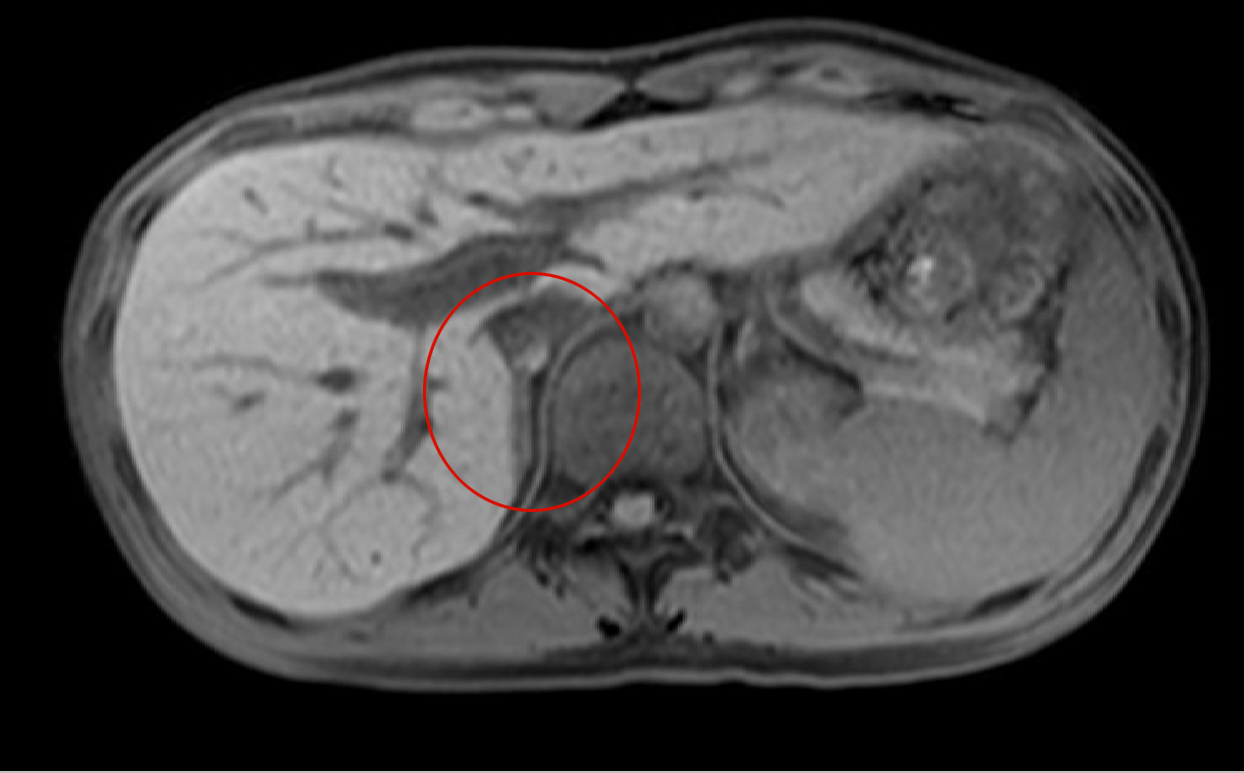

- 【参考症例① 42歳男性】

-

- 副腎腫大と周囲の脂肪組濃度上昇

- 副腎の実質の造影不良

- 被膜には増強効果あり

単純CT

Gd-T1WI